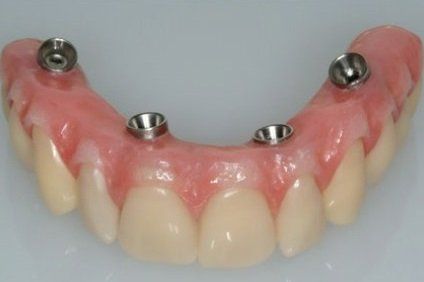

Realizzazione di impianti dentali"All on four" (on five, on six)

La "All on four" è una tecnica a carico immediato di implantologia dentale, studiata per gli edentuli quindi per persone che purtroppo hanno perso tutti o quasi tutti gli elementi dentali presenti in un'arcata.

Può essere eseguita sia nell'arcata dentale superiore che nell'arcata dentale inferiore sempre che le condizione ossee lo rendano possibile, è per questo motivo importante fare un analisi radiografica dettagliata tridimensionale Conebeam.

Grazie ad "All on four" persone costrette alle protesi totali mobili in resina e superiori con palato, possono godere di una nuova dentatura fissa e poco ingombrante.